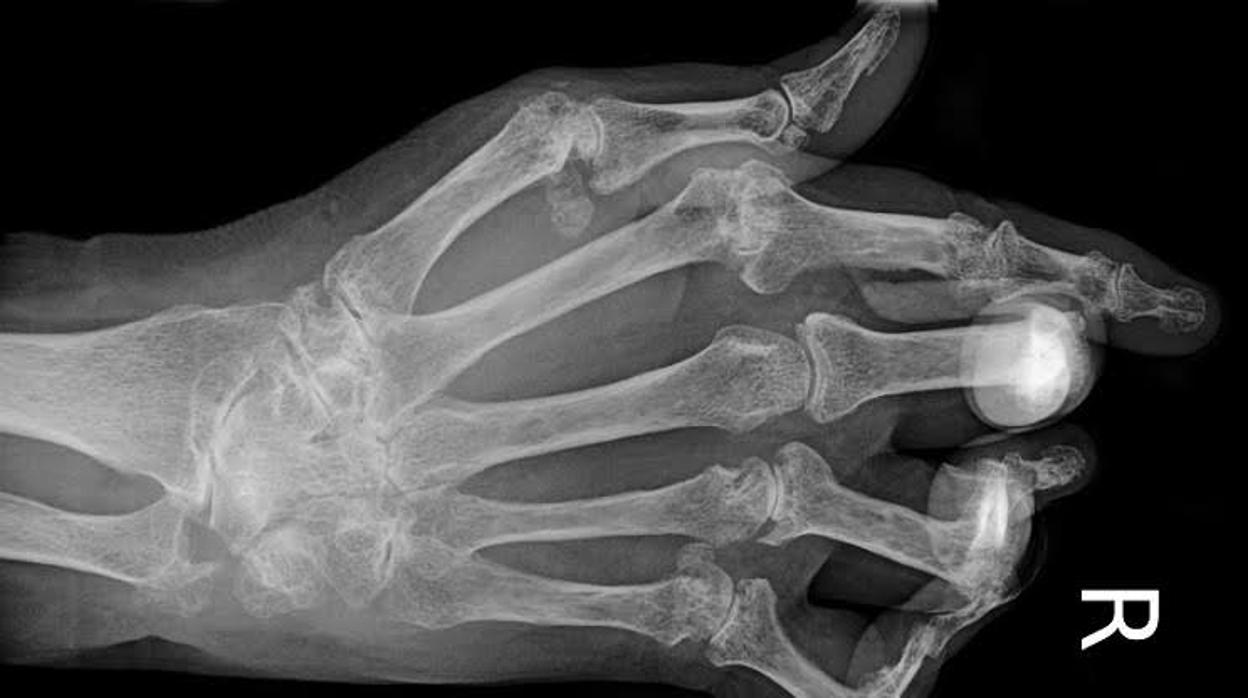

Mano con artritis Archivo

La investigación ofrece datos precisos sobre la prevalencia de enfermedades como artritis reumatoide , artropatía psoriásica, espondilitis anquilosante, lupus erimatoso sistémico, síndrome de Sjögren, artrosis sintomática, fractura osteoporótica, fibromialgia y gota.

Los resultados constatan que más de 5,5 millones de españoles padecen artrosis lumbar, cerca de 880.000 gota, casi 300.000 tienen artritis reumatoide, en torno a 215.000 artritis psoriásica, y algo más de 75.000 lupus eritematoso sistémico.